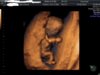

No teraz już widzęraczkami trzyma sie za głowę; ) i brzuszek i kawalek nozek widac

U mnie się udało ładne ujęcie maluszka zrobić bez zniekształceńwg mnie to 3d to porażka. okropnie zdeformowany ten maluch wyszedl